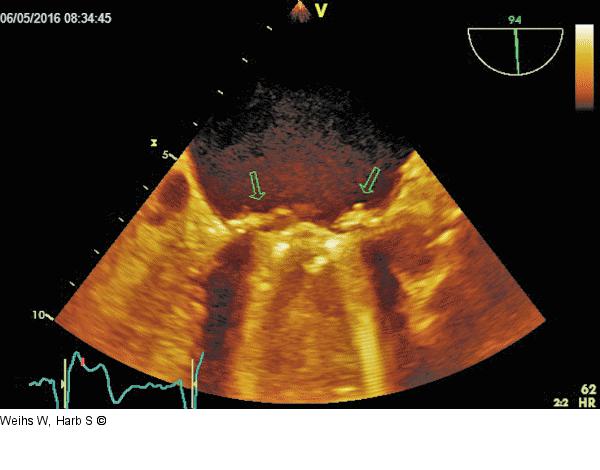

Abbildung 6: TEE Unveränderte Vegetationen nach mehrwöchiger Antibiose |